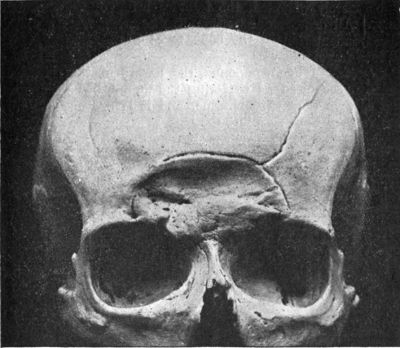

202.Skull of Woman illustrating the appearances of Tertiary Syphilis of Frontal Bone—Corona Veneris—in the Healed Condition408